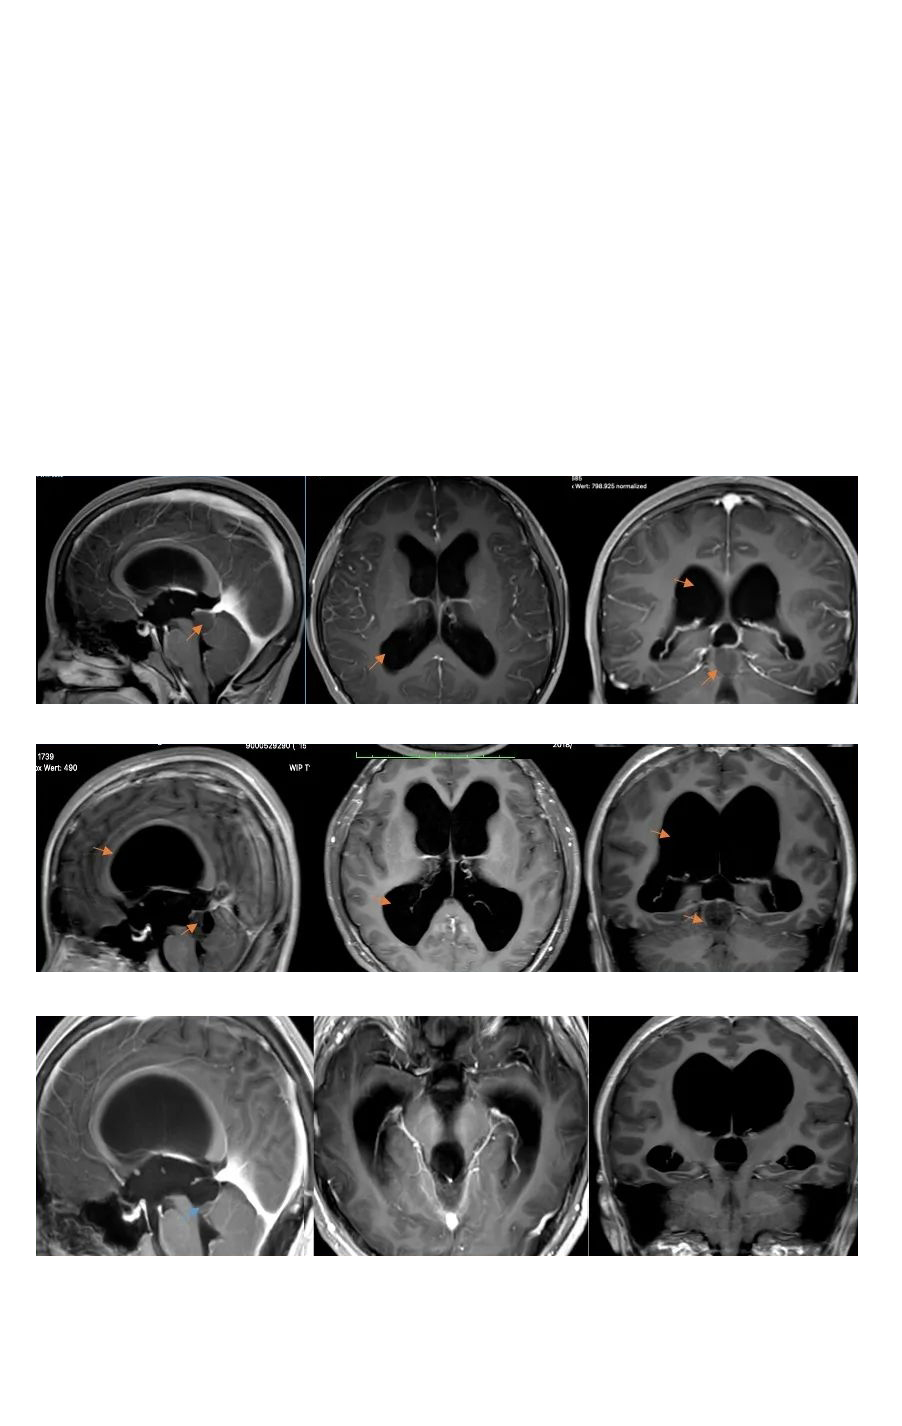

毛細胞型星形細胞瘤是一種預(yù)后較好的低級別膠質(zhì)瘤,不管發(fā)病位置在哪里,手術(shù)全切基本可達到不復(fù)發(fā)的更好效果。在治療中,一次手術(shù)尤為重要,應(yīng)在不損傷患者正常腦組織和功...

INC國際教授毛細胞型星形細胞瘤疑難手術(shù)案例

毛細胞型星形細胞瘤是一種預(yù)后較好的低級別膠質(zhì)瘤,不管發(fā)病位置在哪里,手術(shù)全切基本可達到不復(fù)發(fā)的更好效果。在治療中,一次手術(shù)尤為重要,應(yīng)在不損傷患者正常腦組織和功能神經(jīng)的前提下切除腫瘤,避免復(fù)發(fā)和后遺癥,更大水平好轉(zhuǎn)患者術(shù)后生存質(zhì)量。

另外,鑒于一些腫瘤病發(fā)部位位置較深,解剖結(jié)構(gòu)復(fù)雜,選擇醫(yī)術(shù)、有成功手術(shù)經(jīng)驗的醫(yī)生主刀手術(shù)可更大水平實現(xiàn)保神經(jīng)、保功能、全切腫瘤、無殘留的手術(shù)效果。INC國際神經(jīng)外科醫(yī)生致力國內(nèi)外醫(yī)術(shù)學(xué)術(shù)交流、加強疑難病癥救治,其旗下國際神經(jīng)外科顧問團(World Advisory Neurosurgical Group,WANG)是由國際各發(fā)達國家神經(jīng)外科各亞??浦飨?、宗師級聯(lián)合組成的教授組織,包括以年輕時即是疑難手術(shù)入路重要奠基者、以超群的手術(shù)技術(shù)救治超過40個國家疑難病癥患者的國際神經(jīng)外科聯(lián)合會(WFNS)教育委員會主席Bertalanffy巴特朗菲教授;擅長小兒腦瘤和癲癇治療的兒童神經(jīng)外科專家James T. Rutka教授;十幾位教授們不僅擁有高超的手術(shù)技巧和豐富的臨床經(jīng)驗,還較為重視患者細致神經(jīng)功能的康復(fù),以期提升其生活質(zhì)量、生存預(yù)后。有需者可電話400-029-0925詳細垂詢學(xué)術(shù)交流、遠程咨詢、聯(lián)合咨詢或教授主刀等。